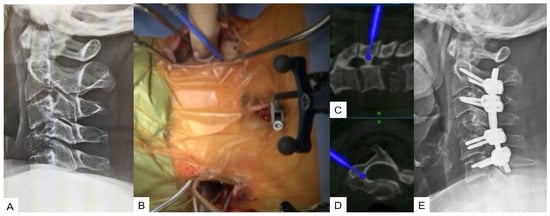

Transdiscal Screw for DISH (Diffuse Idiopathic Skeletal Hyperostosis) Fracture

- Tanaka, M.; Fujiwara, Y.; Uotani, K.; Kamath, V.; Yamauchi, T.; Ikuma, H. Percutaneous transdiscal pedicle screw fixation for osteoporotic vertebral fracture: A technical note. Interdiscip. Neurosurg. 2021, 26, 00903. [Google Scholar] [CrossRef]